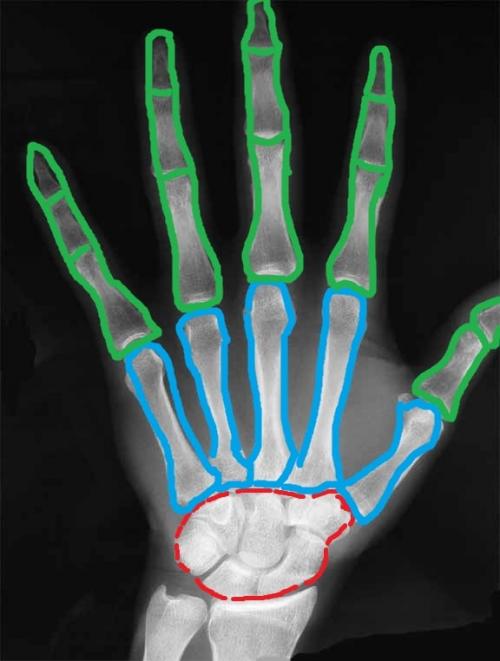

Я решил немного раскрасить этот скучный рентгеновский снимок. Красным цветом я выделил запястье, голубым — пясть, а зелёным — кости пальцев (фаланги).

Кости запястья (ossa carpi)

К костям запястья относят восемь маленьких плотных косточек, которые располагаются в два ряда — проксимальный и дистальный . Чтобы не запутаться в них, следует придерживаться принципам, которые я описывал в статье о том, как учить анатомию человека .